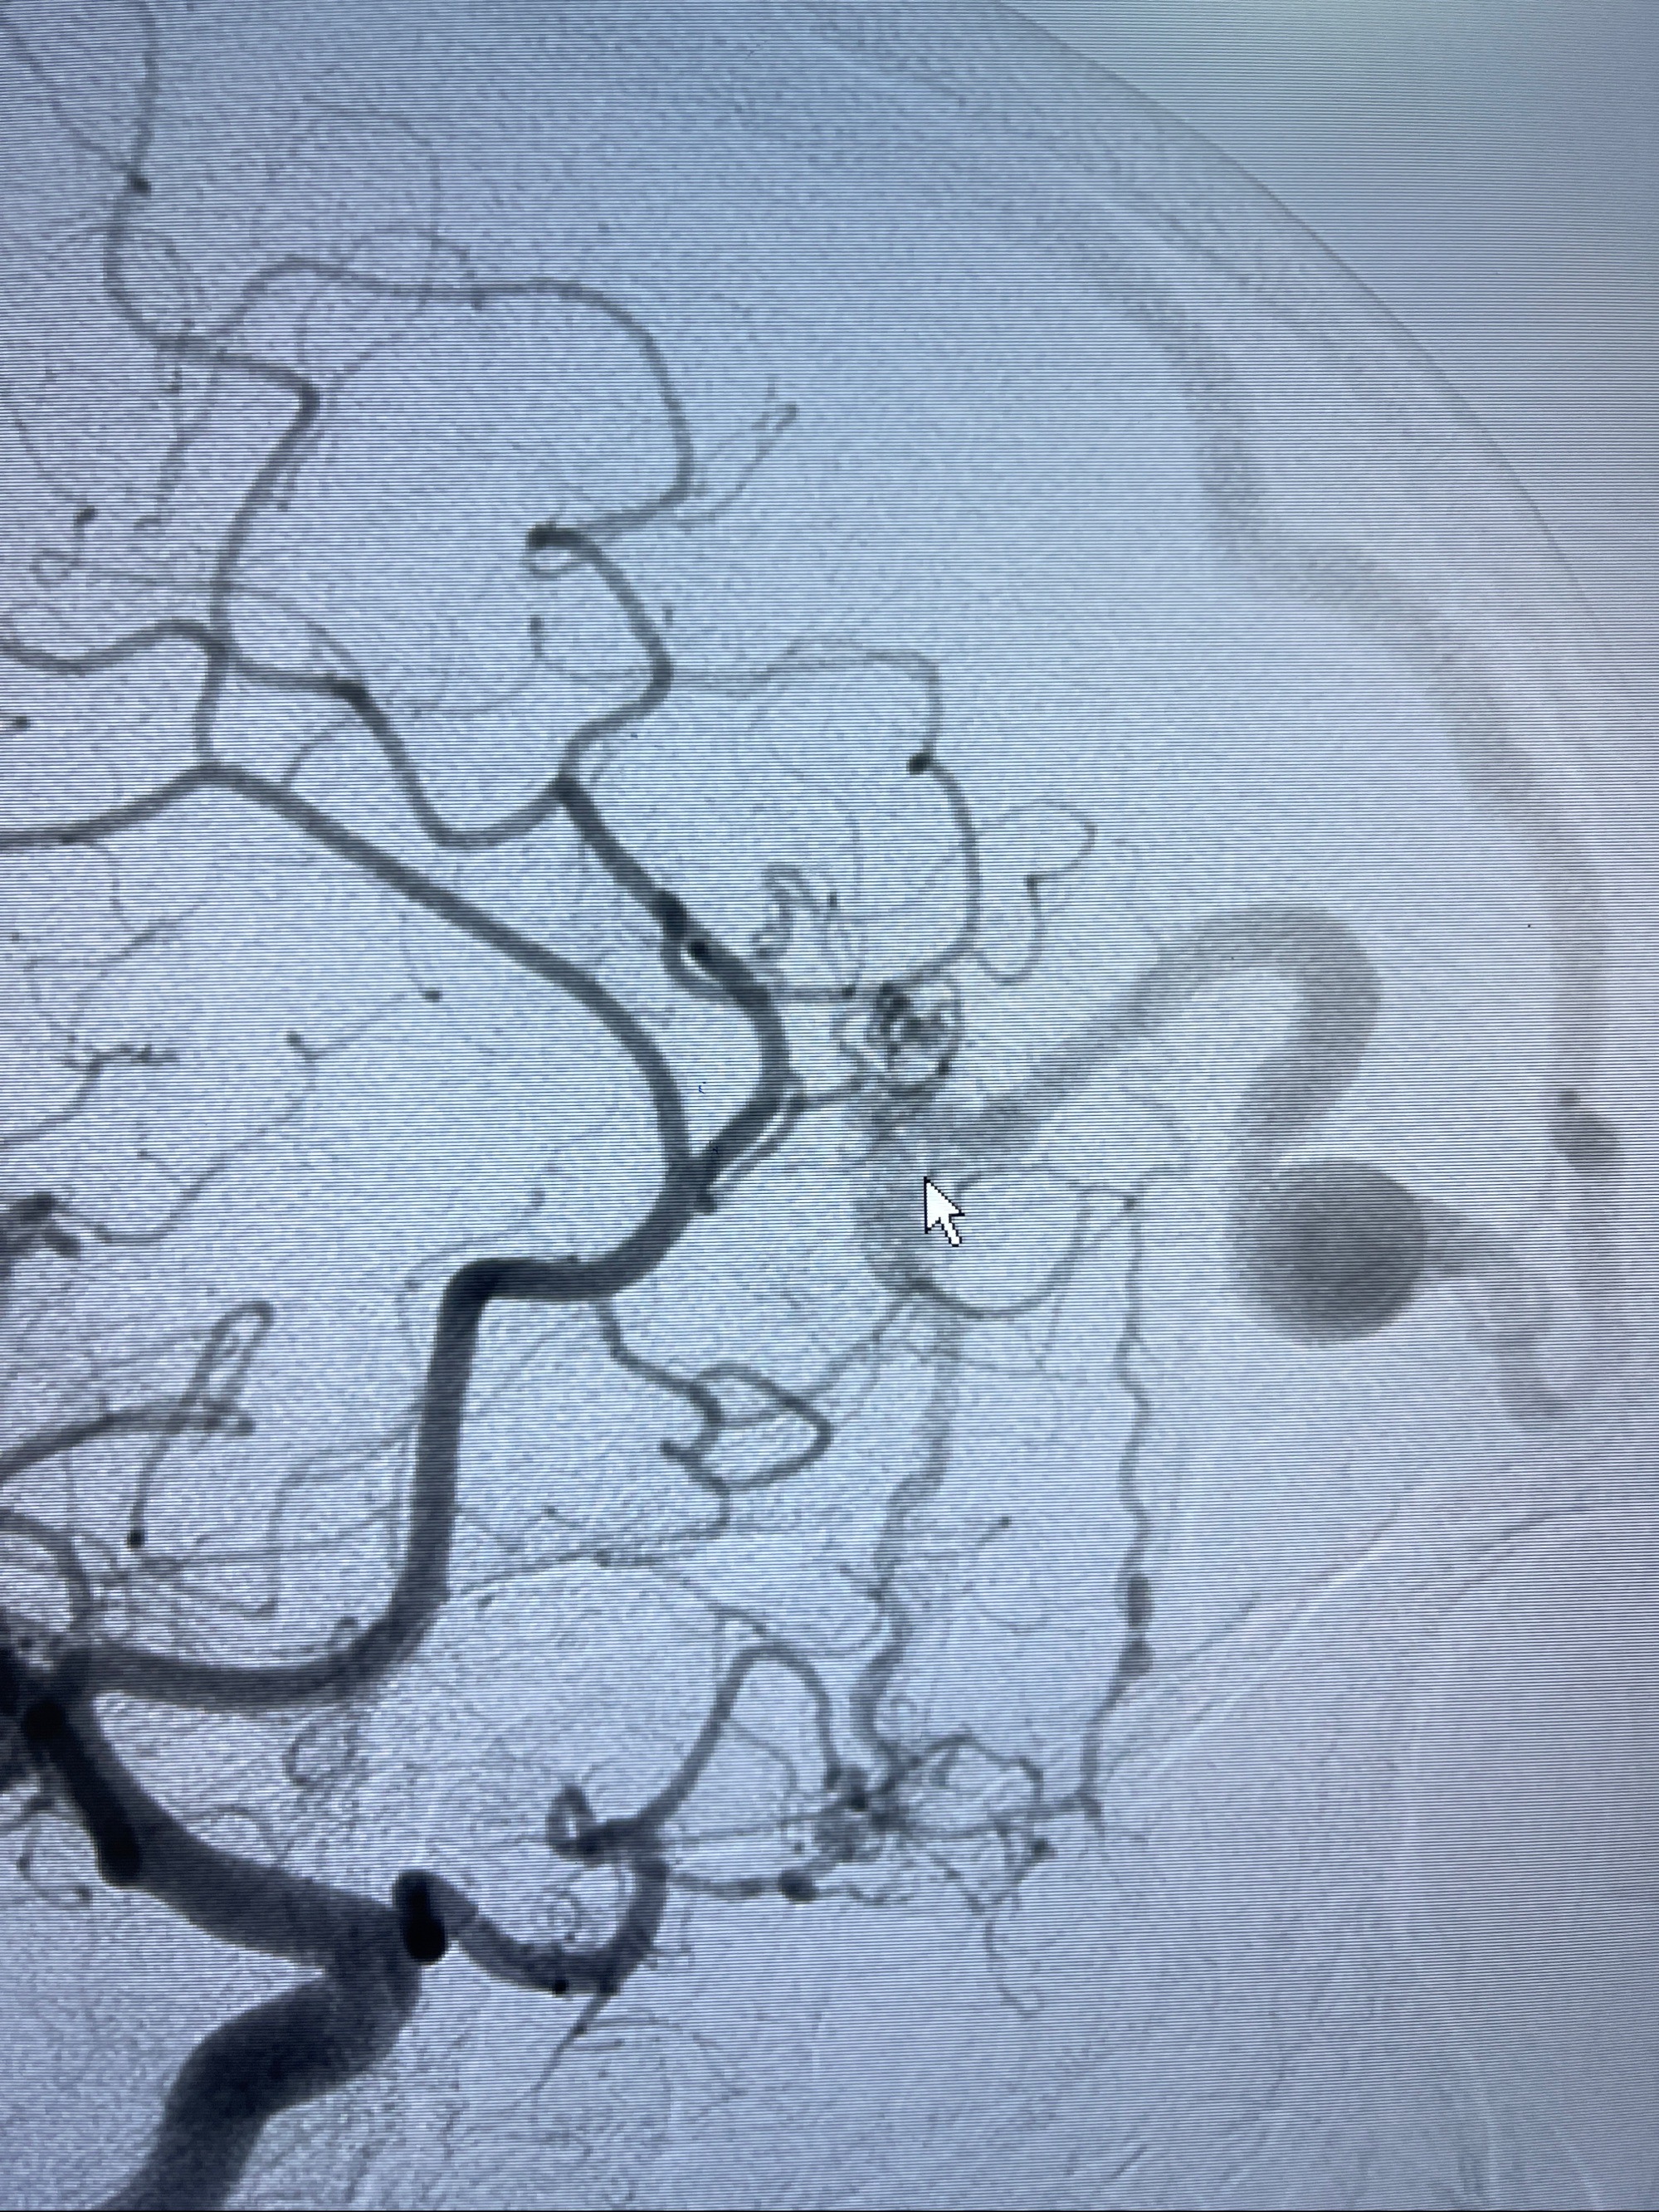

2023-09-13全脑血管造影:前颅底硬脑膜动静脉瘘,供血动脉为双侧胼周动脉、眼动脉脑膜支,静脉向上矢状窦方向引流